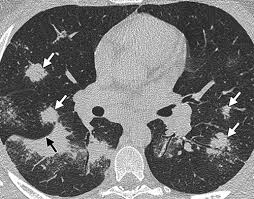

The decrease in other more severe symptoms is wheezing which if. Sarcoidosis is often identified as swollen hilar lymph nodes found in chest radiography during routine physical checkups. Sarcoidosis is a somewhat common pulmonary disease, but the concurrence of lung cancer and sarcoidosis in the same patient is very rare. Read about sarcoidosis, a chronic lung disease. By magdalena kegel | august 12, 2016.

Frontiers Sarcoidosis As An Autoimmune Disease Immunology from www.frontiersin.org It typically affects young adults and initially presents with one or more of the following. Helen has now had treatment for her lung cancer and is recovering well. A case of primary lung cancer associated with sarcoidosis. We report a patient with concomit. Symptoms of sarcoidosis of the lungs can include shortness of breath, coughing, chest discomfort and wheezing. The decrease in other more severe symptoms is wheezing which if. For these people, the symptoms are not usually severe. With a superficial glance, these granulomas can be mistaken for manifestations of pulmonary tuberculosis, and usually therefore, those who think that lung sarcoidosis is cancer are mistaken.

Board certification in internal medicine. Treated her nodal involvement as small cell lung cancer. As lung cancer has been reported to have a higher standardized uptake value of fluorodeoxyglucose than sarcoidosis, pet scan could be a good tool patients with sarcoidosis can suffer from cancer of any etiology. Sarcoidosis is an inflammatory disease that affects one or more organs but most commonly affects the lungs and lymph glands. Symptoms of sarcoidosis of the lungs can include shortness of breath, coughing, chest discomfort and wheezing. No tumor cells are detected in beck's disease. Sarcoidosis is a rare disease caused by inflammation. The initial signs and symptoms of bladder cancer are often mistaken for those of a urinary tract infection or kidney stone. It is not known whether the trigger that initiates the immune disturbance is a foreign substance, chemical, drug, virus, or some other substance. The decrease in other more severe symptoms is wheezing which if. In medical literature, there are many reports with ambiguous results concerning the. Although no one can predict how sarcoidosis will progress in an individual patient, some clues as to disease course can be gained from patient symptoms, findings from physical. For many people with sarcoidosis, symptoms often improve without treatment within a few months or years.